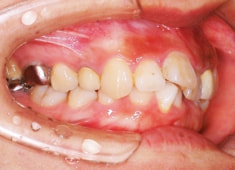

治療前